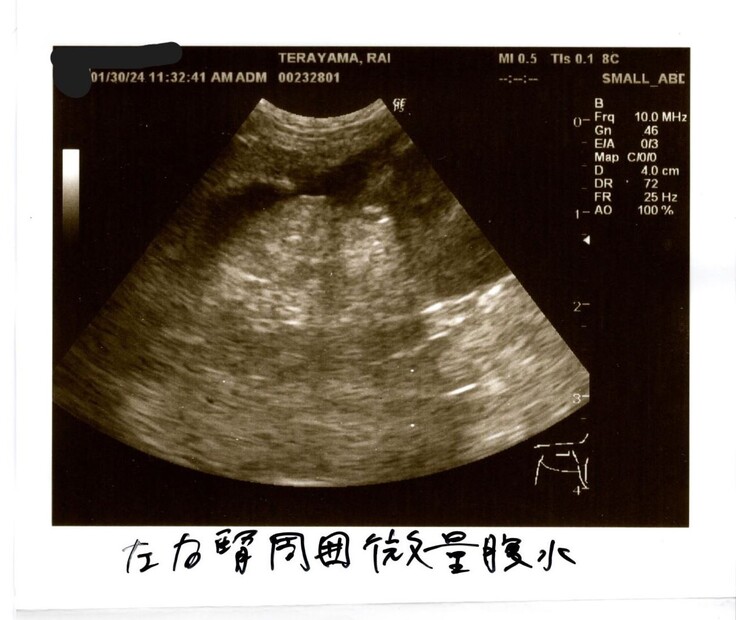

③左右の腎周囲に微量の腹水あり